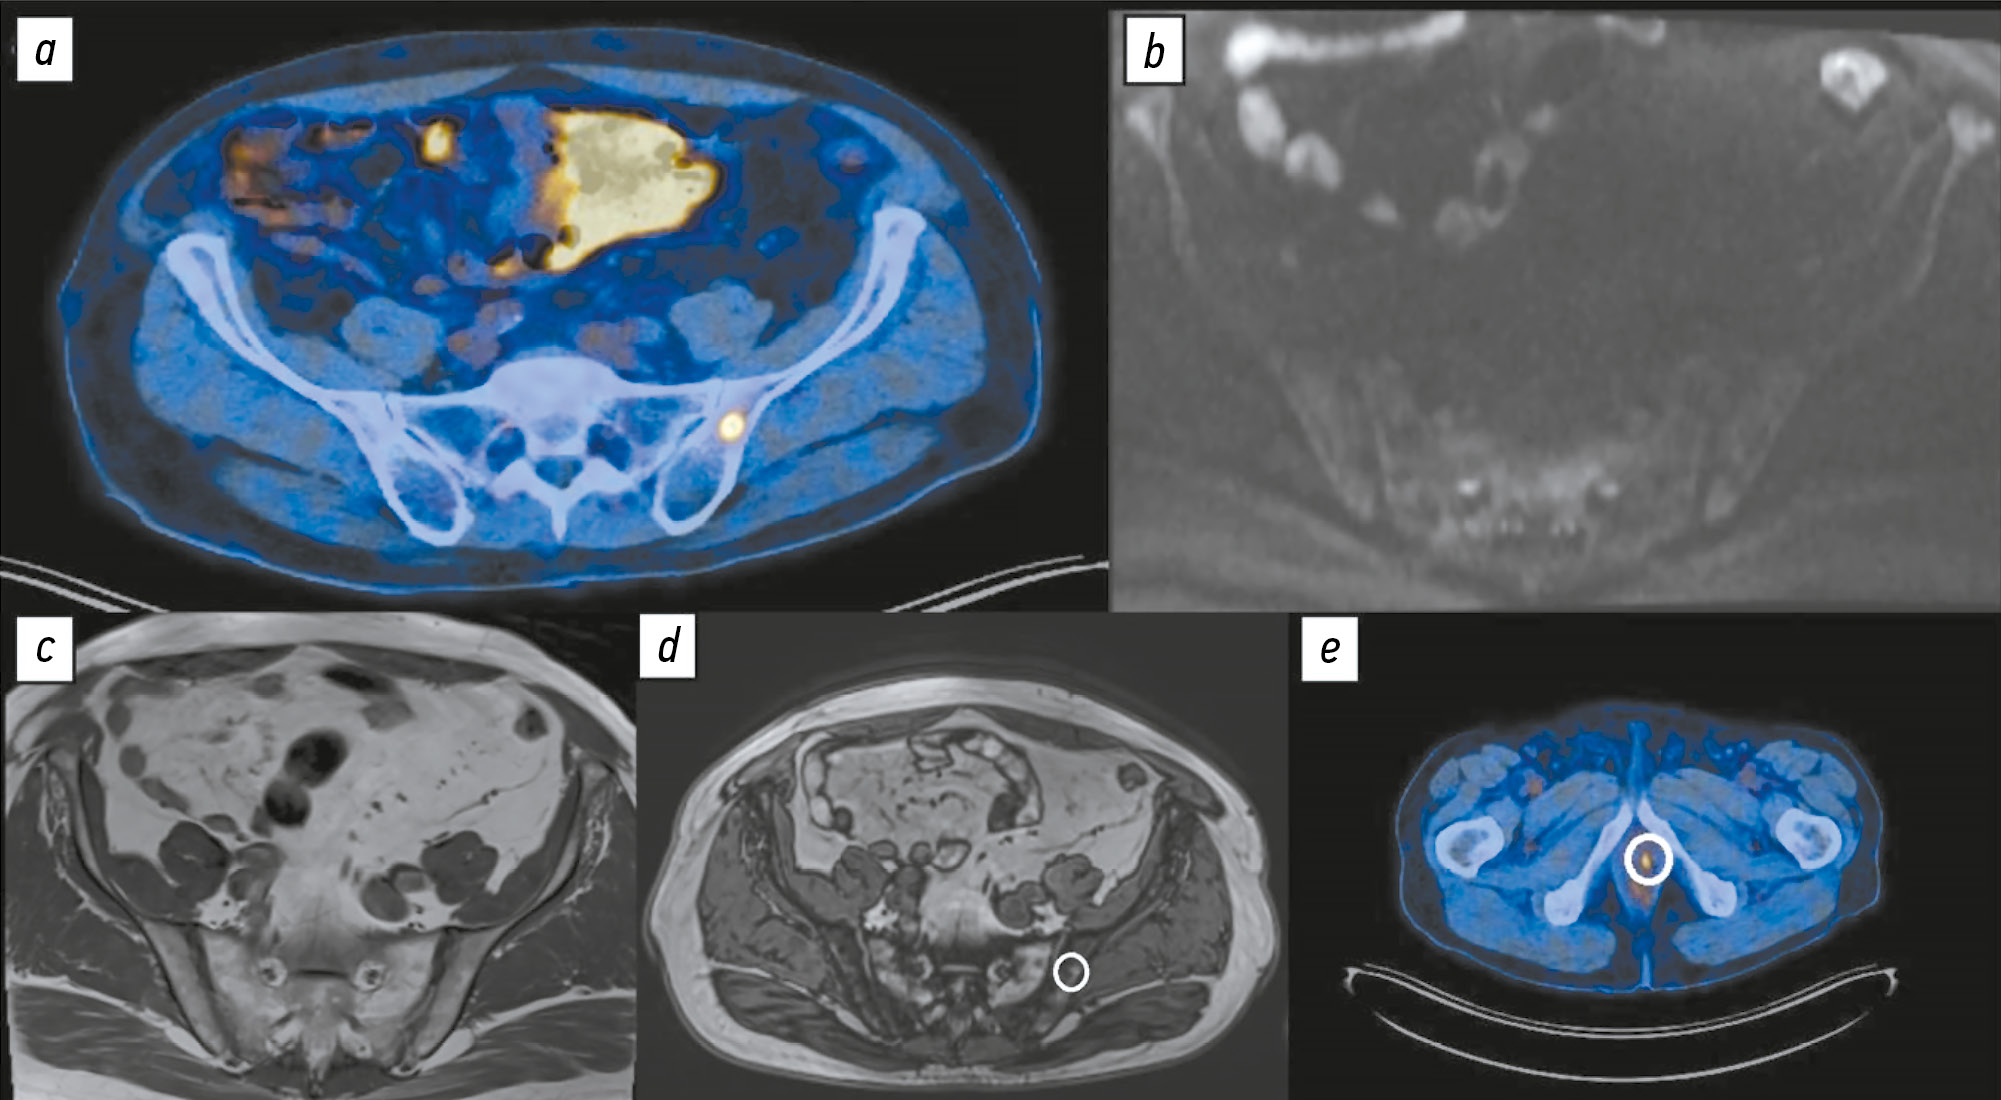

Comparison of the diagnostic accuracy of whole-body diffusion-weighted imaging and 18F-prostate-specific membrane antigen-1007 positron emission tomography combined with computed tomography for detecting bone metastases in prostate cancer

BACKGROUND: The increasing availability of 18F-prostate-specific membrane antigen-1007 (18F-PSMA-1007) for prostate cancer staging highlighted its advantages, particularly its higher spatial resolution compared to analogs. Moreover, accumulating scientific data indicate an increase in false-positive findings, predominantly in bones, which may lead to unwarranted upstaging of the disease. Diffusion-weighted imaging may be used for the early detection of bone metastases.

AIM: This study aimed to assess and compare the diagnostic accuracy of whole-body 18F-PSMA-1007 positron emission tomography combined with computed tomography and whole-body and pelvic bone diffusion-weighted imaging in patients with prostate cancer.

METHODS: A retrospective single-center selective study was conducted. The imaging results of 119 patients with prostate cancer were divided into two groups: group 1 comprised 40 pairs of 18F-PSMA-1007 positron emission tomography combined with computed tomography and whole-body diffusion-weighted magnetic resonance imaging scans, and group 2 included 79 pairs of similar studies, with magnetic resonance imaging performed only for the pelvic bones. The diagnostic studies were performed at an inter-study interval ≤14 days. The metastatic bone lesions detected in different anatomical regions was counted using data from 18F-PSMA-1007 positron emission tomography combined with computed tomography and magnetic resonance imaging. Lesions were considered true positives if confirmed by additional magnetic resonance imaging pulse sequences and/or follow-up observation.

RESULTS: Whole-body diffusion-weighted imaging demonstrated higher specificity (58.1%) for detecting bone metastases than 18F-PSMA-1007 positron emission tomography combined with computed tomography (51.06%). However, its sensitivity was lower: 93.22% versus 97.55%.

CONCLUSION: Despite its advantages, 18F-PSMA-1007 positron emission tomography combined with computed tomography shows a high rate of false-positive bone findings. These are most commonly noted in the ribs, vertebrae, and pelvic bones. Suspicious bone lesions should be further evaluated to avoid unjustified disease upstaging. Thus, whole-body magnetic resonance imaging with diffusion-weighted sequences and selective fat signal suppression can be used.